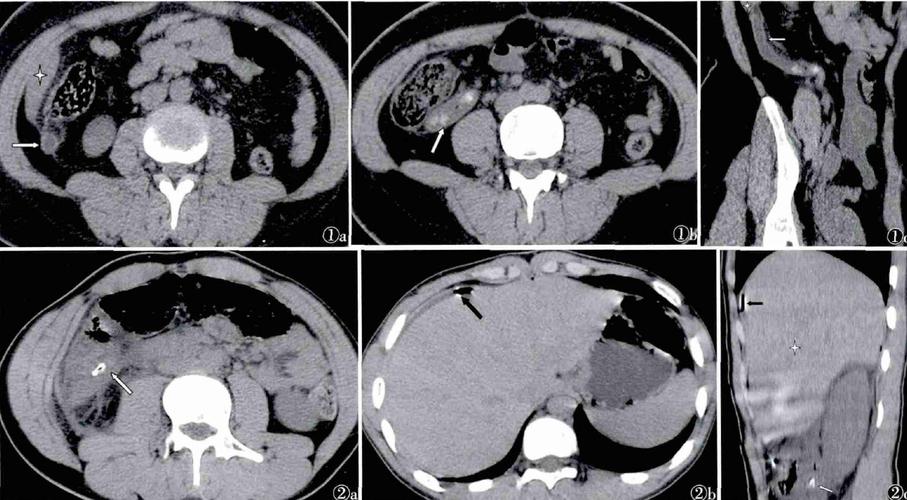

文摘:高位急性阑尾炎的临床及 ct 诊断分析

急性阑尾炎的ct表现

打基础急性阑尾炎ct诊断